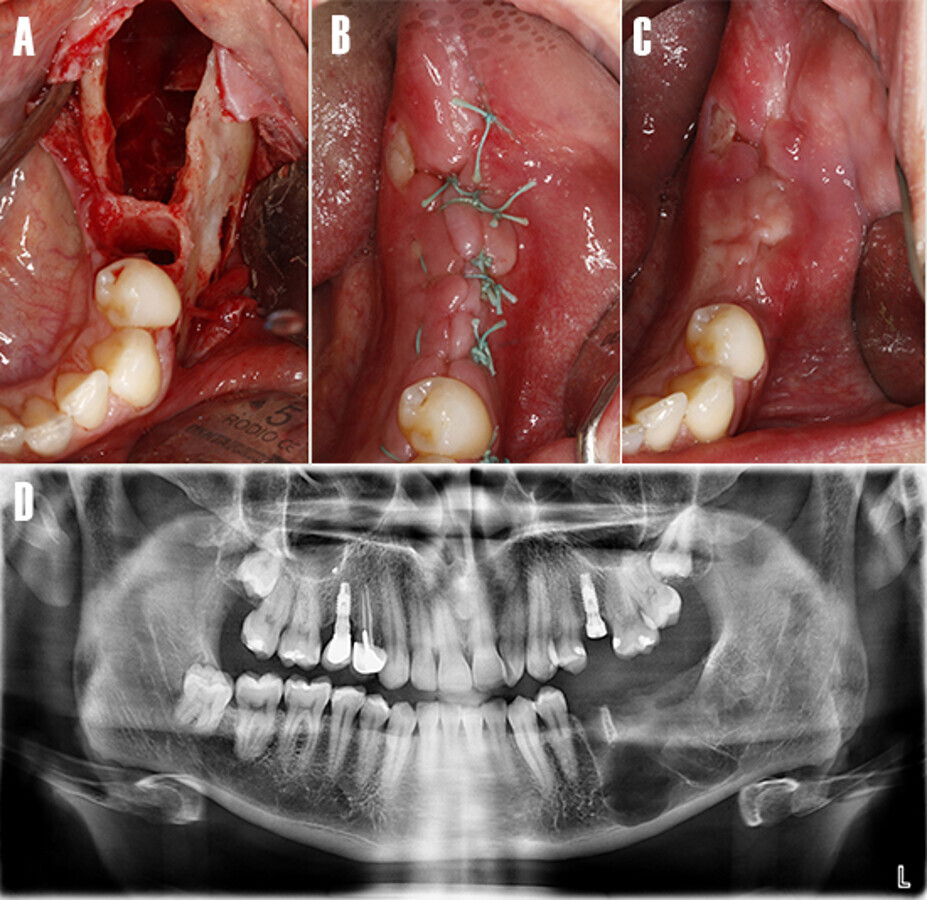

Tras un periodo de osteointegración de tres meses se realizó una cirugía de acceso para colocar el pilar de cicatrización de implante 3.7 y posterior registro con escáner intraoral (3shape Trios®, Copenaghen, Denmark) (Fig. 13), para la confección de la prótesis atornillada definitiva (Fig. 14)

Figura 13. Fase protésica. A) A las 12 semanas de la cirugía de implantes, se realizó una segunda cirugía para colocar el pilar de cicatrización a nivel de 3.7. B) Pilar de cicatrización atornillado. C) A los 15 días se procede tomar registros de impresión con un escáner intraoral. Nótese los scan-bodies en posición.